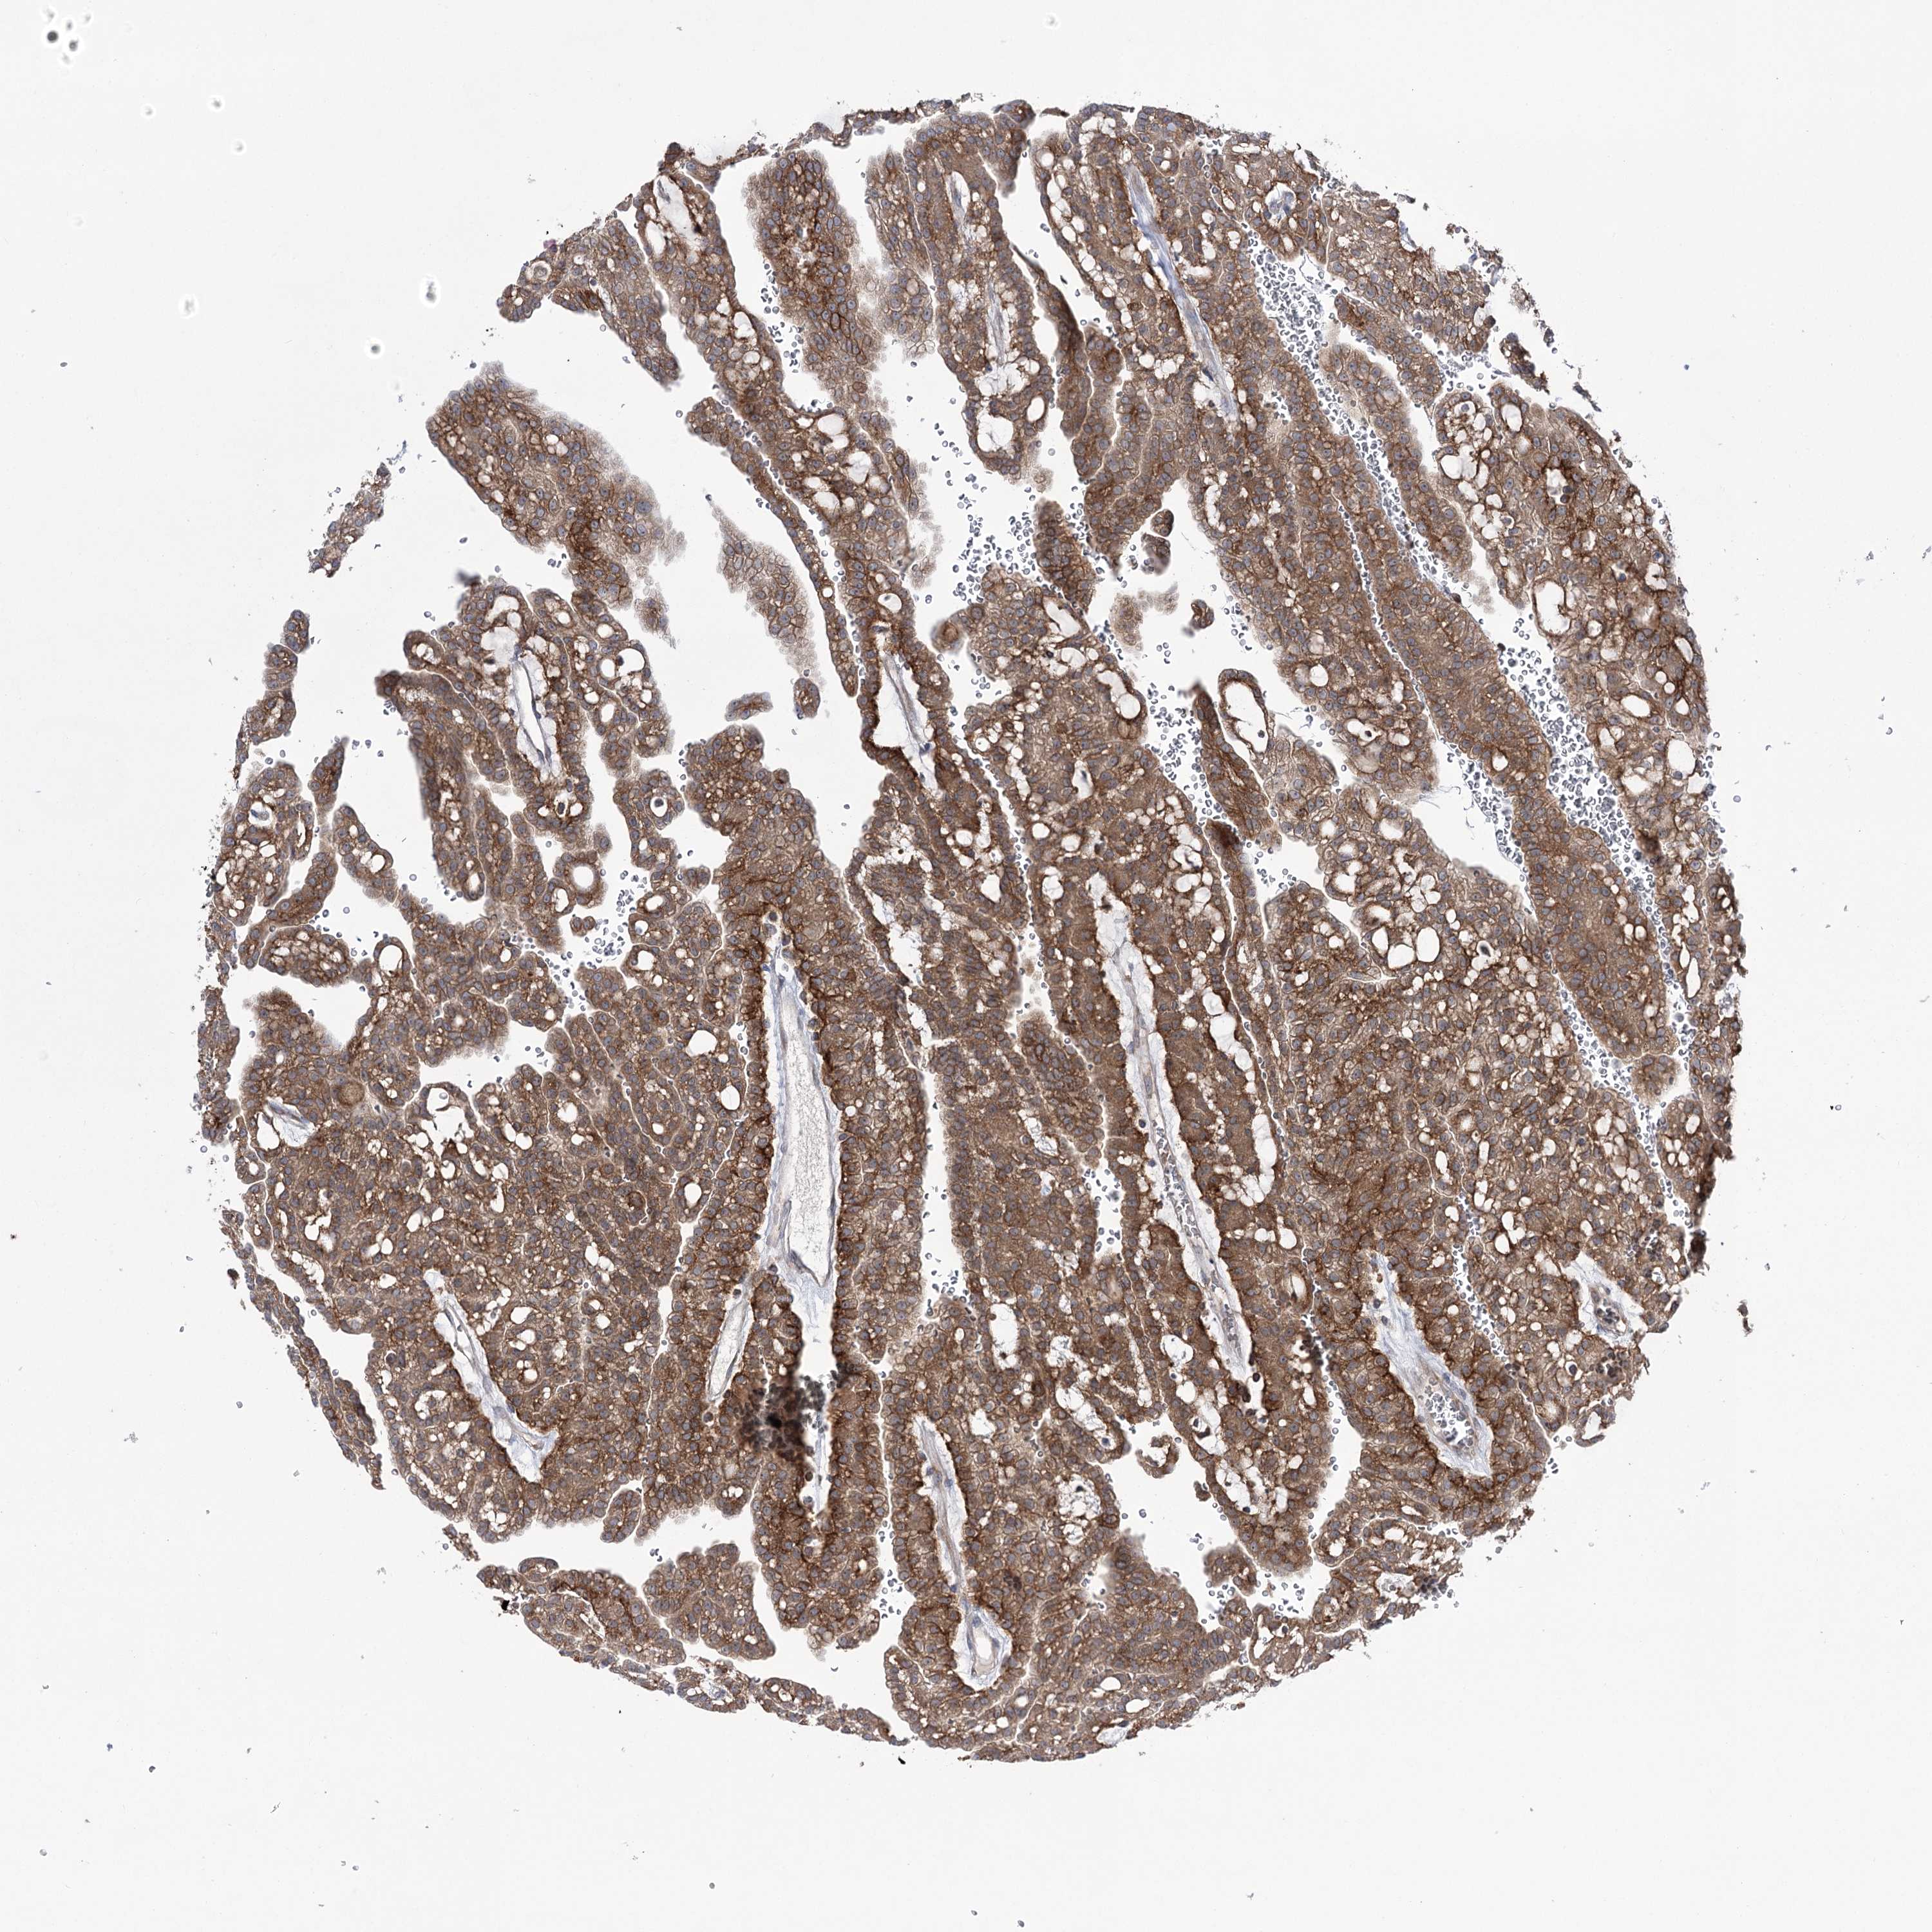

KIDNEY RENAL PAPILLARY CELL CARCINOMA (TCGA) - Interactive survival scatter ploti

The Survival Scatter plot shows the clinical status (i.e. dead or alive) for all individuals in the patient cohort, based on the same data that underlies the corresponding Kaplan-Meier plots. Patients that are alive at last time for follow-up are shown in blue and patients who have died during the study are shown in red.

The x-axis shows the expression levels (FPKM) of the investigated gene in the tumor tissue at the time of diagnosis. The y-axis shows the follow-up time after diagnosis (years). Both axes are complimented with kernel density curves demonstrating the data density over the axes. The top density plot shows the expression levels (FPKM) distribution among dead (red) and alive patients (blue). The right density plot shows the data density of the survived years of dead patients with high and low expression levels respectively, stratified using the cutoff indicated by the vertical dashed line through the Survival Scatter plot. This cutoff is automatically defined based on the FPKM cutoff that minimizes the p-score. The cutoff can be changed by dragging the vertical line or by entering a cutoff value in the square labeled "Current cut-off".

Under the Survival Scatter plot the p-score landscape (black curve; left axis) is shown together with dead median separation (red curve; right axis). Dead median separation is the difference in median mRNA expression between patients who have died with high and low expression, respectively. It is calculated as follows: median FPKM expression of dead patients with high expression - median FPKM expression of dead patients with low expression. This is intended to aid the user in visually exploring custom cutoffs and the associated p-scores and dead median separation.

Individual patient data is displayed and can be filtered by clicking on one or more of the category buttons on the top of the page. Categories describing expression level and patient information include: high, low, alive, dead, female, male and tumor stages. The scale of the x-axis can be toggled between linear and log-scale by clicking on the "x log" button. Mouse-over function shows TCGA ID, patient information and mRNA expression (FPKM) for each patient.

& Survival analysisi

Kaplan-Meier plots summarize results from analysis of correlation between mRNA expression level and patient survival. Patients were divided based on level of expression into one of the two groups "low" (under cut off) or "high" (over cut off). X-axis shows time for survival (years) and y-axis shows the probability of survival, where 1.0 corresponds to 100 percent.

ZNF622 is not prognostic in Kidney Renal Papillary Cell Carcinoma (TCGA)